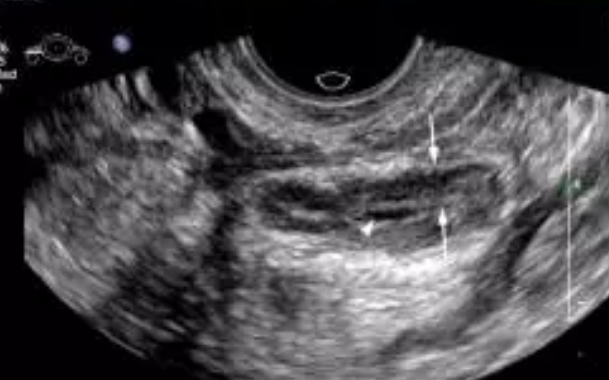

試管嬰兒前有必要做宮腔鏡檢查嗎 宮腔鏡檢查后多久可以做試管嬰兒

很多女性由于很多因素的影響,沒有辦法受孕,于是會通過試管嬰兒的形式,而很多女性都會有一個疑惑,那就是試管嬰兒